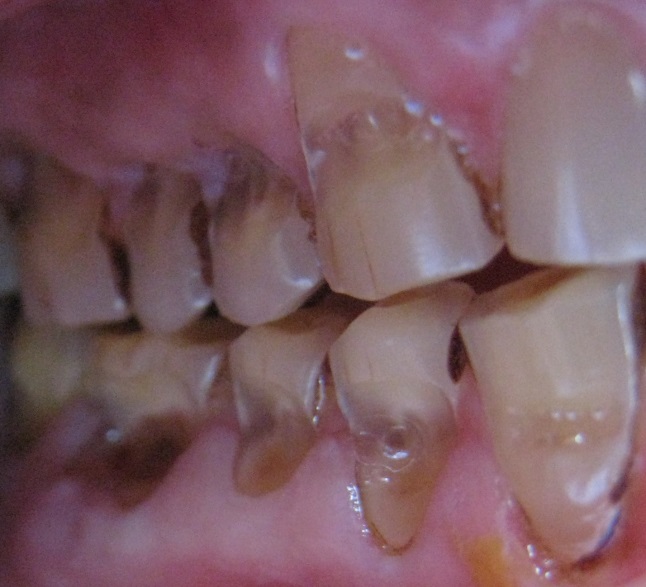

What Is Abrasion In Dental .   tooth abrasion is where your teeth start to lose enamel due to some sort of outside.  dental abrasion refers to the wearing away of tooth enamel, which is the hard outer layer of the tooth. It can occur due to various factors, such as. If you’ve noticed the signs of.   this condition, called dental abrasion, can occur when any foreign object causes friction against your teeth and gradually wears away the enamel on the surface. This wears away the enamel, the outer layer of the tooth, making it more susceptible to. However, bigger problems arise when your bite is out of alignment, often causing more friction in places less prepared for it.  tooth abrasion is a form of tooth wear that is caused by the repetitive grinding or scrubbing of the teeth against a hard surface. Dental abrasion is a condition that occurs when the tooth enamel wears away due to external factors. So, when two or more teeth come together, even with regular chewing with an ideal bite, some abrasion will occur. It can manifest as the loss of tooth structure, particularly.   abrasion is the result of repeated contact between a tooth and something hard, like teeth.